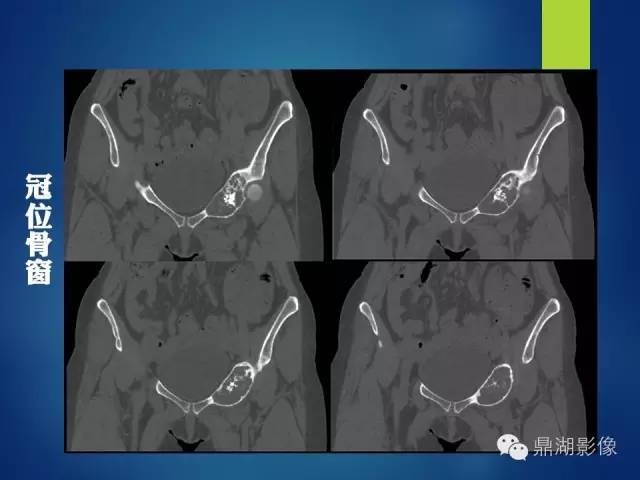

影像表现:

左侧耻骨可见一不规则略低于软组织密度影,周围骨皮质变薄,其内可见丝瓜囊样密度增高影,未见明显骨膜反应及骨折线。

X 线表现为侵蚀骨质破坏,可见软组织肿块。CT 能更清楚地显示其钙化,但不广泛。肿块含水量多,故在CT像上表现为低密度;黏液型软骨肉瘤较普通型软骨肉瘤更常见出血,在MRI的T1WI、T2WI 上均表现为高信号, (肿块) 增强扫描肿块呈轻度强化。

影像学上的表现基本反映了病理学的特点:

(1) 溶骨性改变,X 线、CT 表现为低密度,MRI 上,T1WI为低信号,T2WI 为高信号;

(2) 出现“环形弧样”钙化;

(3) 浸润性特征,骨内膜呈扇形增厚并常见软组织肿块,增强肿块为边缘强化或分隔样强化。